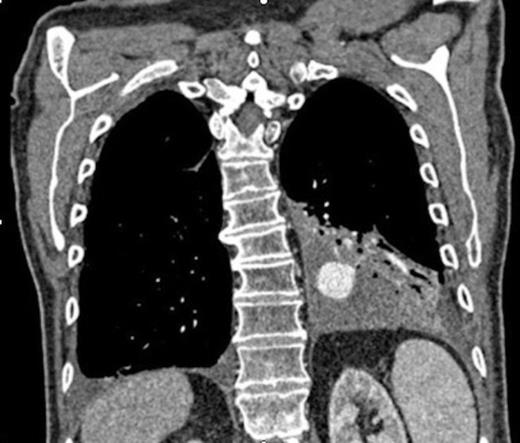

Digital subtraction angiography post deployment of the AVP 4 device in the PA branch feeding the aneurysm (arrow). No residual or collateral filling seen

Coronal reconstruction of CTPA taken 2 days after embolisation demonstrating successful ongoing exclusion of the PA aneurysm. Note the AVP (arrow) and continued filling of unaffected lower lobe segmental pulmonary arterial branches